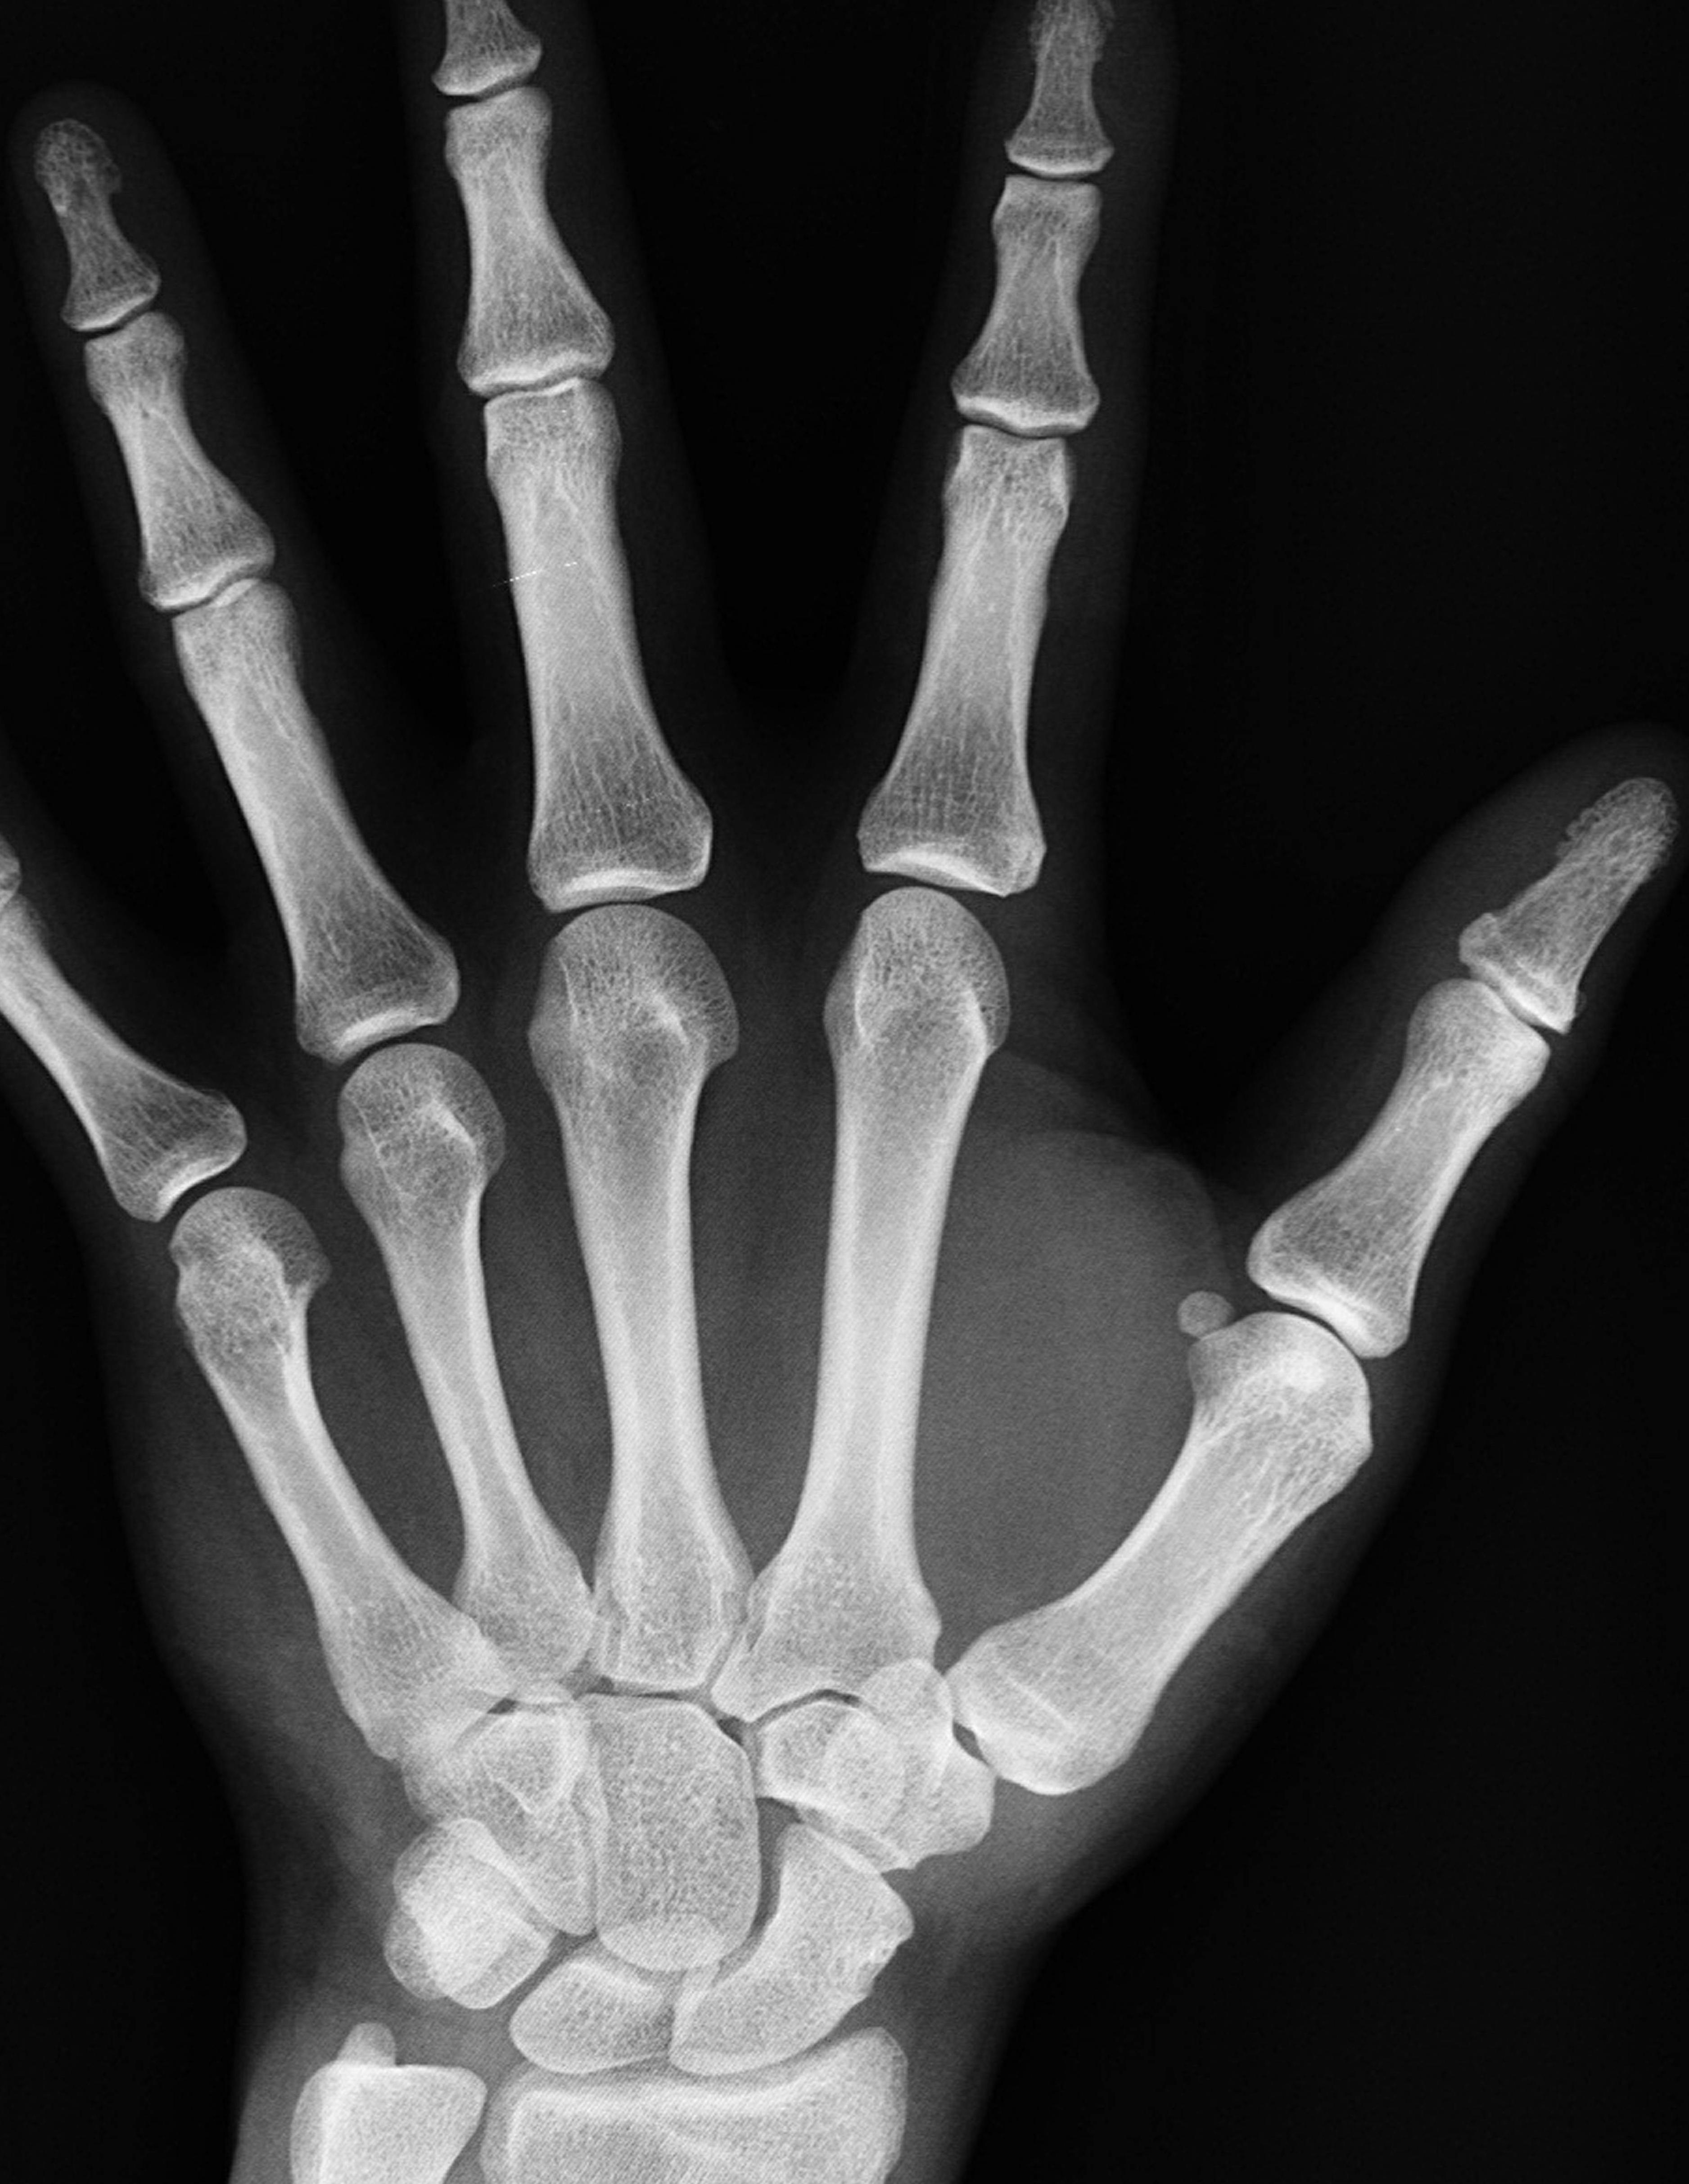

OSTEOPOROSIS & BONE DENSITY

WHAT YOU NEED TO KNOW AS YOU AGE

ging is a journey we all take, one filled with wisdom, memories, and a deeper understanding of what truly matters. But as we blow out more candles on our birthday cakes, certain silent changes are happening inside our bodies that we may not immediately notice. One of the most important, yet often overlooked, is what’s happening with our bones.

Our bones are the foundation of our body, quite literally. They hold us upright, protect our organs, anchor our muscles, and store essential minerals like calcium and phosphorus. Yet, as we age, our bones can become more fragile. This process is called osteoporosis, and it affects millions of people, most of them unknowingly until a fall, a fracture, or a sudden back pain forces them to take notice.

UNDERSTANDING BONE DENSITY AND OSTEOPOROSIS

Bones aren’t just static structures like concrete; they’re living tissues that are constantly being broken down and rebuilt. When we're young, the building happens faster than the breakdown. However, somewhere around our 30s, that balance begins to shift. The rebuilding slows, while the breakdown picks up pace. Over time, this can lead to a gradual loss of bone mass and strength.

Osteoporosis, which literally means “porous bone,” occurs when the bones become so weak and brittle that even a minor fall or bump can result in a fracture. The most common fractures linked to osteoporosis happen in the hip, spine, and wrist. These aren’t just painful injuries; they can be life-altering, particularly in older adults.

The truth is, osteoporosis is often called a “silent disease” because it develops slowly and without symptoms. You might not feel your bones weakening; there’s no headache, no fever, no rash. Everything seems fine, until it's not. That’s why awareness and early testing are so important.

Because osteoporosis doesn’t announce itself with loud symptoms, the only reliable way to know your bone health is to get tested. This is where bone density testing, also called a DEXA scan, comes in.

A DEXA (dual-energy X-ray absorptiometry) scan is a quick, painless, and non-invasive test that measures bone mineral density (BMD). It’s usually performed on the lower spine and hips, the areas most vulnerable to fractures. The scan compares your bone density to that of a healthy young adult and gives you a score called a T-score. The lower the score, the higher your risk of fracture.

This test can be a game-changer. It doesn’t just tell you where you stand; it helps guide your next steps. Whether that means starting treatment, changing your diet, incorporating weightbearing exercises, or simply monitoring your progress over time, testing empowers you to take control of your bone health.

Doctors usually recommend a bone density test for women over 65 and men over 70. But if you have risk factors like early menopause, previous fractures, or a family history of osteoporosis, you may need to be tested earlier. I tend to have low calcium levels because I had thyroid cancer and also had several of my parathyroid glands removed. Consequently, I started having bone density scans earlier and continue to have them done every two years.